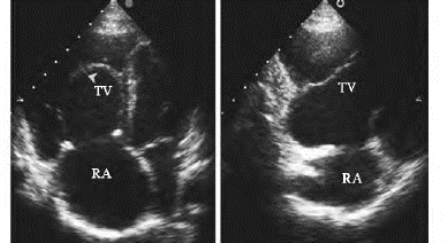

图17-5 三尖瓣下移畸形二维超声图

左图:心尖四腔切面,显示三尖瓣隔叶(箭头所示);右图:右室流入道长轴切面,显示三尖瓣后瓣下移